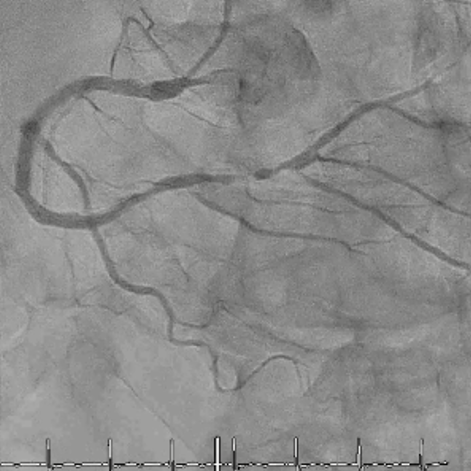

CAG

RCA distalの高度石灰化狭窄病変